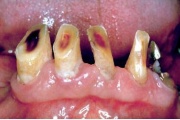

Lutipudelikaariese kahjustused